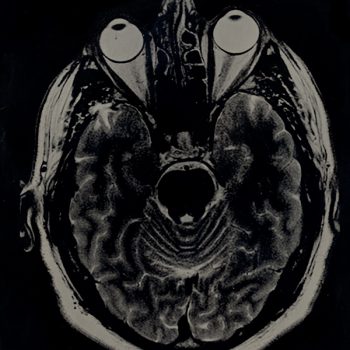

Galleries of the World Wet Plate Collodion Days

Gallery - RESTORED

Here we have Image-Uploads since 2009 that we could restore to the Website. If you have Images from the World Wet Plate Day since 2009, please Login and upload it to your account and year.Zoom Image